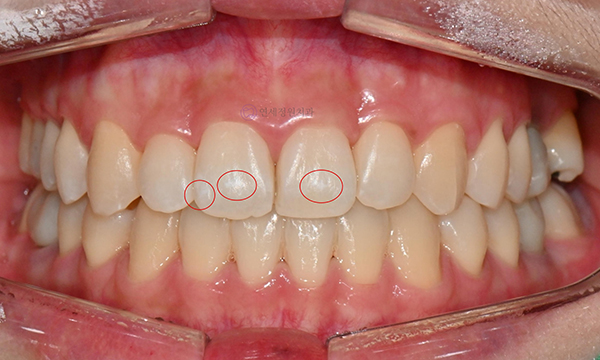

본 20대 여자 환자분은 약 한 달전 교정 치료를 끝마친 후에 앞니에 화이트 스팟이 생겼다는 이유로 감사하게도 경기도에서 저희 치과까지 찾아와주셨습니다. 일반적으로 교정 치료 후 생긴 반점치는 장치 형태 주변으로 생기는데, 본 환자의 경우 앞니 2개에 심하지는 않지만 중앙 부분에 화이트 스팟이 생겼습니다.